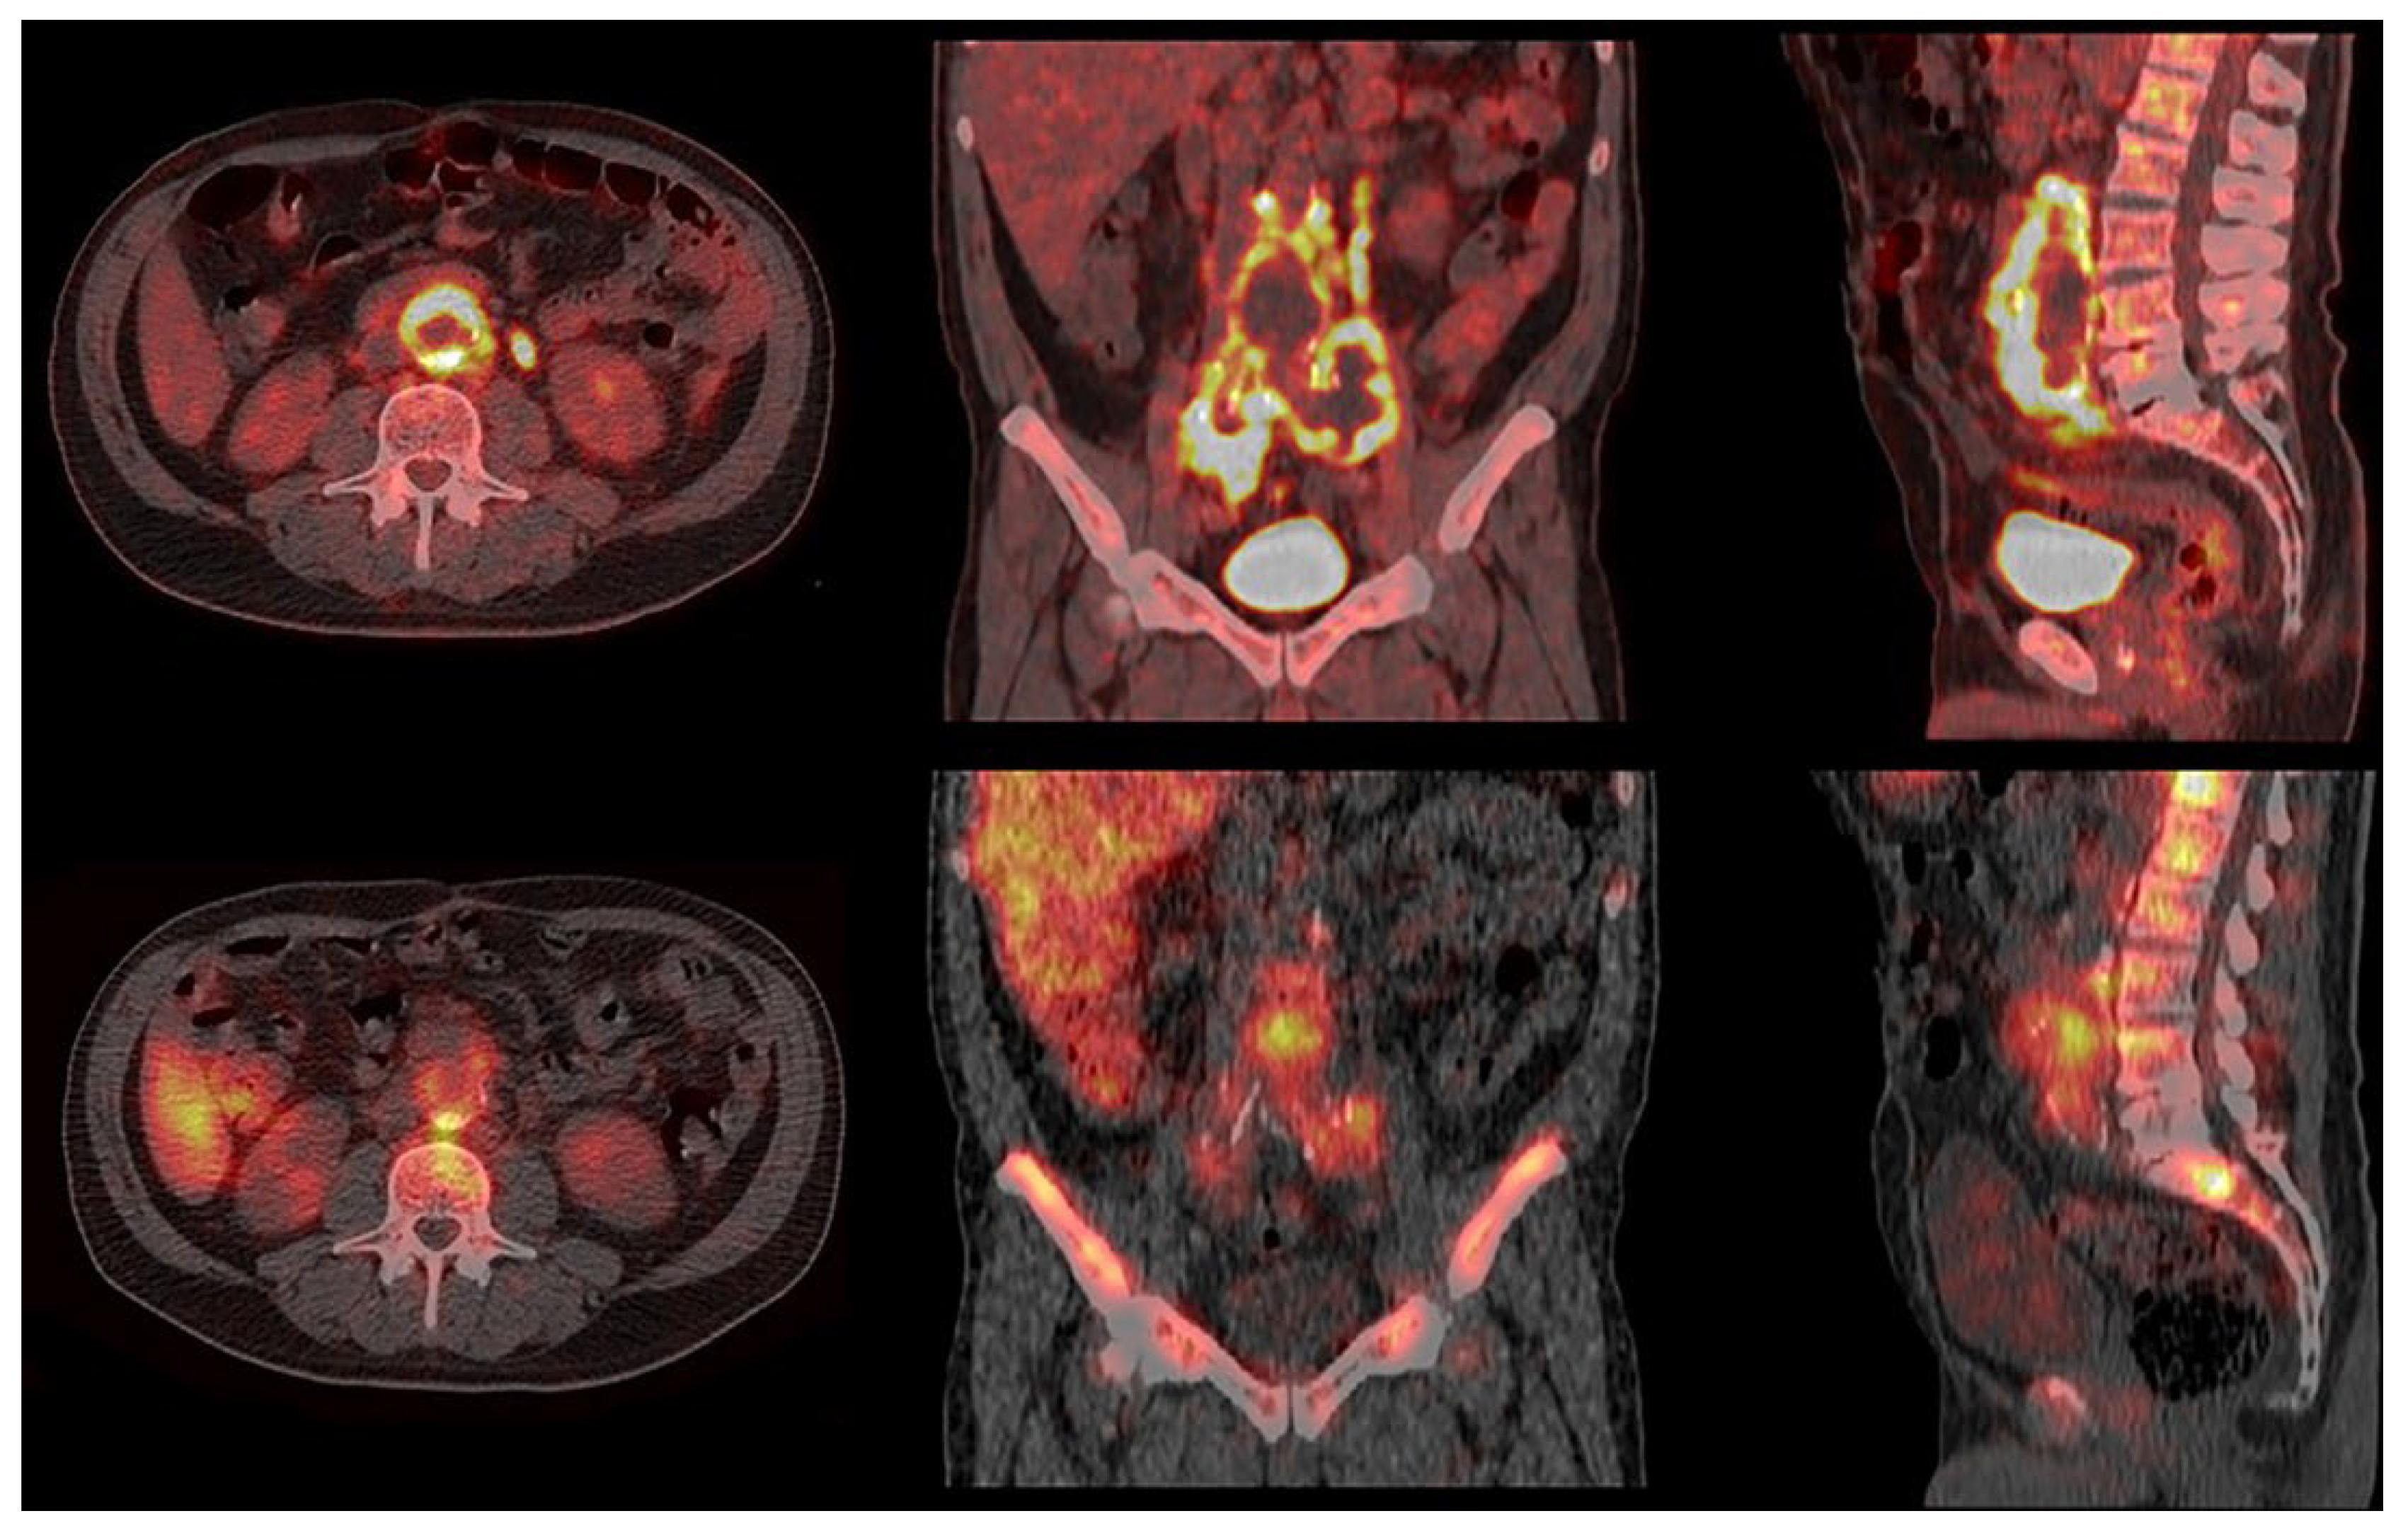

3. Results